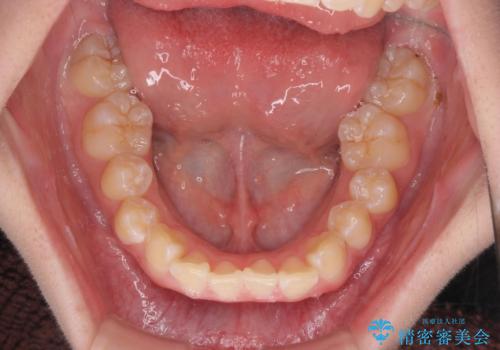

前歯のがたつき気になる。インビザラインモデレート

- 前歯のがたつきが気になるとの事で来院。

マウスピース矯正希望でしたのでインビザラインモデレートで治療を行いました。

がたつきが無くなり満足して頂けました。